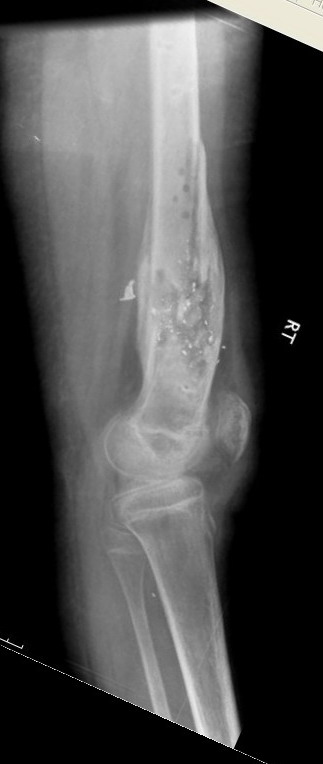

Выше представлены рентгенограммы открытого оскольчатого перелома нижней трети голени X-rays of Compound Comminuted # Distal/3 Lt Tibia

Операционные снимки перед и после наложения аппарата Илизарова In operation room before and after Ilizarov apparatus has been applied

Послеоперационные рентгенограммы Postoperative X-rays

В нижнем ряду представлены рентгенограммы после окончательной репозиции. And final reduction after Hexapod program has been finished